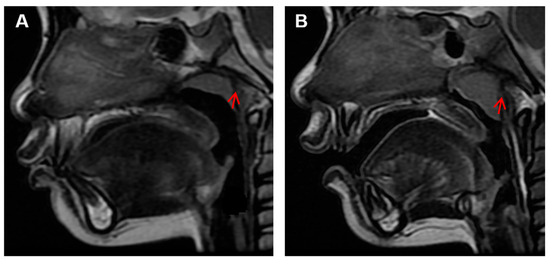

Influences of Adenoid Hypertrophy on Children’s Maxillofacial Development

This study aims to investigate the association between adenoid hypertrophy and facial development. A total of 388 children aged 1–13 years old who had undergone head MRI in Foshan Maternal and Child Health Hospital were collected, including 196 hypertrophic cases and 192 normal [...] Read more.

This study aims to investigate the association between adenoid hypertrophy and facial development. A total of 388 children aged 1–13 years old who had undergone head MRI in Foshan Maternal and Child Health Hospital were collected, including 196 hypertrophic cases and 192 normal cases. The maxillofacial soft tissue indicators were measured and compared. The A/N ratio and adenoid thickness consistently increased with age in the hypertrophic group and the A/N ratio reached a maximum value three years earlier than the normal group. The pharyngeal airway space, vallecula of epiglottis to anterior plane distance of the third/fourth cervical vertebrae, angle of convexity, total angle of convexity, and the nasolabial angle in the hypertrophy group were smaller than those in the control group (p < 0.05). The thickness of adenoids, palate height, palate length, and tongue length in the hypertrophy group exceeded that of the control group (p < 0.05). To conclude, adenoid hypertrophy was associated with craniofacial features such as a convex facial profile, a narrowed nasopharyngeal airway, an elongated and heightened palate, a lengthened tongue or a lower tongue position. These findings emphasize the importance of early intervention for children with adenoid hypertrophy to mitigate potential adverse effects on maxillofacial development. Full article